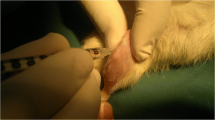

Rats were anesthetized with diethyl ether and given a single intra-articular injection of 2.5 mg MIA (Sigma–Aldrich, St. Louis, MO, USA) into the infrapatellar ligament of the right knee [20]. MIA was dissolved in 0.9 % normal saline and administered in a 25-µL volume. The rats were arbitrarily divided into eight groups containing six rats each. Subsequently, the rats were treated with normal saline (vehicle-treated MIA group), 2, 10, or 20 mg/kg of SHINBARO by intra-articular administration (intra-articular SHINBARO group; IAS group), 20 or 200 mg/kg of SHINBARO by oral administration (oral SHINBARO group; OS group), and 5 mg/kg of diclofenac by oral administration (diclofenac group) once daily for 21 days. Rats treated with normal saline, and not MIA, were used as a control group (Table 1). The SHINBARO concentrations and MIA injection volume were selected based on previous evaluations [21]. After 21 days of treatment, the animals were euthanized and blood samples were collected for serum isolation. The femurs were dissected and stripped of soft tissue for analysis of the trabecular microarchitecture.

Histopathological analysis

The right knee joints from the tibia to the distal metatarsal including the tarsal joint were resected and fixed with 10 % neutral-buffered formalin for 24 h at 4 °C. The fixed specimens were decalcified with 20 % formic acid for 3 days and embedded in paraffin. Sections of the tissue specimens were acquired from the paraffin blocks at 5 µm thickness, deparaffinized, and rehydrated in the order of xylene, absolute alcohol, and 50 % alcohol. The rehydrated sections were stained with hematoxylin and eosin (H&E) for observation of morphological changes in the articular tissues and safranin-O fast green (SOFG) for evaluation of the proteoglycan (PG) contents.

We performed H&E staining for the articular cartilage surfaces of the femoral condyle and tibial plateau to determine whether IAS treatment restored the damaged surface of the knee joint toward healing. The vehicle-treated MIA group revealed severe irregular abrasions with rough edges around the femur and tibia, indicative of bone lysis, swelling, and tendency for patellar displacement (Fig. 3). This damage was significantly attenuated with the appearance of smoother articular cartilage surfaces by IAS (20 mg/kg) treatment. MIA-induced articular cartilage damage was also restored in the positive control group treated with diclofenac. SOFG staining, which stains PGs and is indicative of the degree of degeneration of cartilaginous tissue [22], was performed to observe the changes in morphology of the cartilaginous tissues. The SOFG-stained control group exhibited normal cartilage PG staining, while the vehicle-treated MIA group revealed severely damaged cartilage with marked fibrillation and PG depletion. Treatment with SHINBARO or diclofenac significantly suppressed the MIA-induced loss of PG and prevented cartilage damage (Fig. 3).

Histopathological analysis of the knee joint tissues after treatment of SHINBARO in MIA-induced OA rat model. The knee joint tissues from MIA-induced OA rat model which was treated with vehicle, SHINBARO or diclofenac were stained with hematoxylin and eosin (H&E) and Safranin O-fast green (SOFG) (magnification ×100)